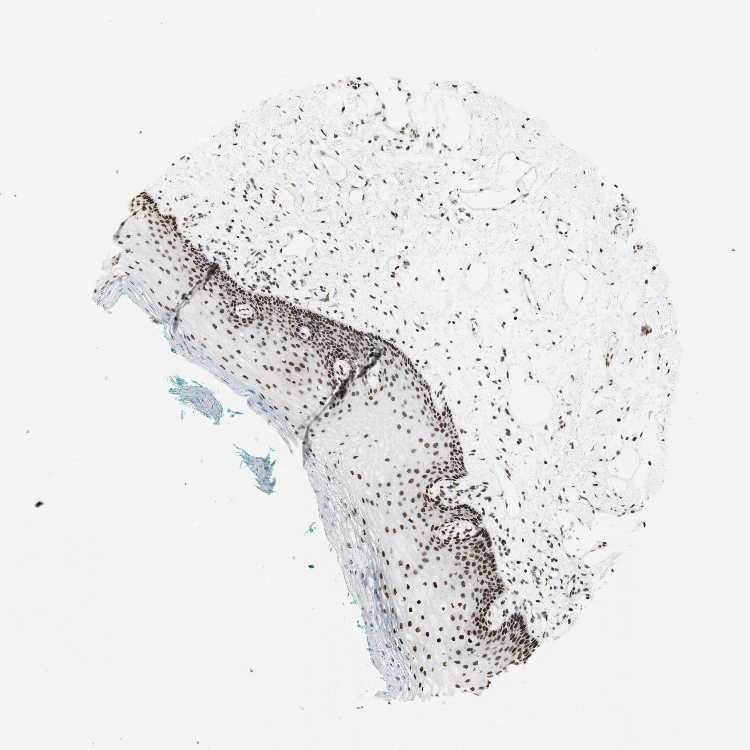

TISSUE PRIMARY DATA ORAL MUCOSA Show tissue menu

Oral mucosa

ORAL MUCOSA - Antibody stainingi

Antibody staining in the annotated cell types in the current human tissue is reported as not detected, low, medium, or high, based on conventional immunohistochemistry profiling in selected tissues. This score is based on the combination of the staining intensity and fraction of stained cells.

Each image is clickable and will lead to virtual microscopy that enables deeper exploration of all samples and also displays staining intensity scores, fraction scores and subcellular localization as well as patient and tissue information for each sample.

Antibody HPA001666Antibody CAB012403

Squamous epithelial cells HighHigh